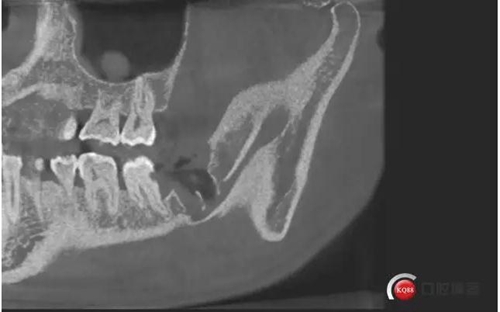

CBCT神經(jīng)管標(biāo)線,可以看到標(biāo)線不能連續(xù),中間被阻斷。

下面拔除后的片子,可以清楚的看到,牙根穿破神經(jīng)管。

拔牙前后對比一下,(拔除前)

1500633362_825152.jpg拔除后。 可以看到神經(jīng)管皮質(zhì)骨的不連續(xù)。